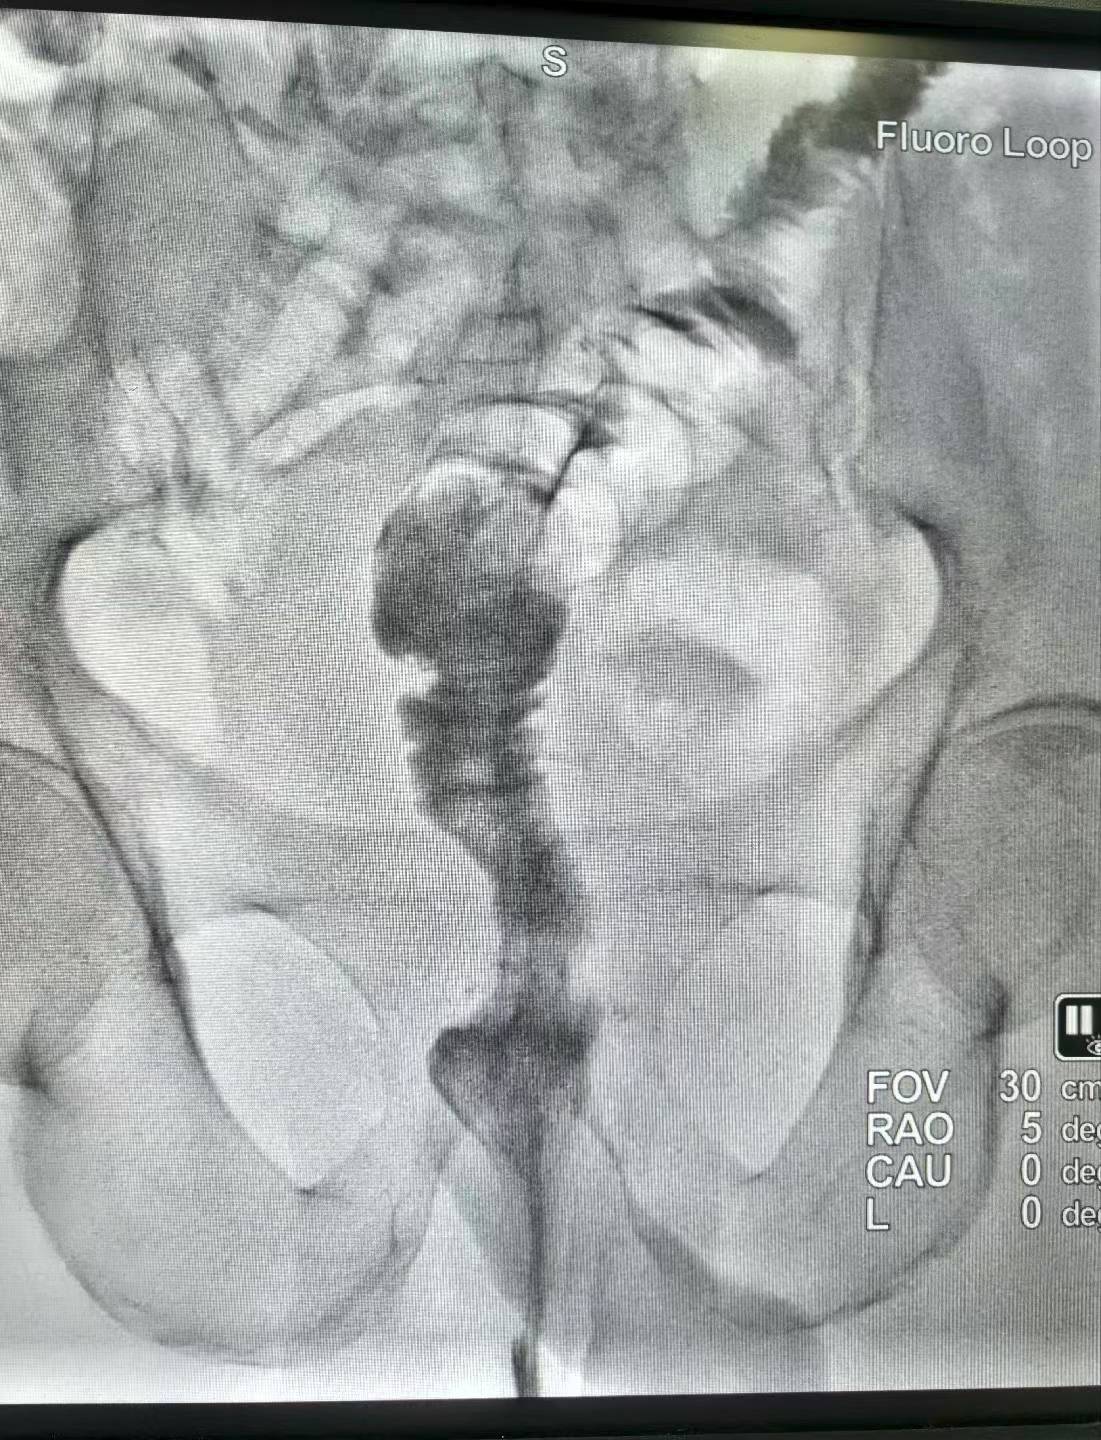

直肠癌术后吻合口狭窄(难治型)球囊扩张术。上午一台直肠癌术后吻合口狭窄经肛行球囊扩张术,球囊充分扩张后狭窄解除。介入球囊扩张对良性难治性狭窄,安全有效,术后即可排便顺畅。